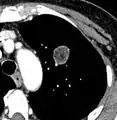

Low attenuating nodule (in this case a fat containing hamartoma).[9]

Cavitation with relatively thick wall, in this case aspergilloma).[9]